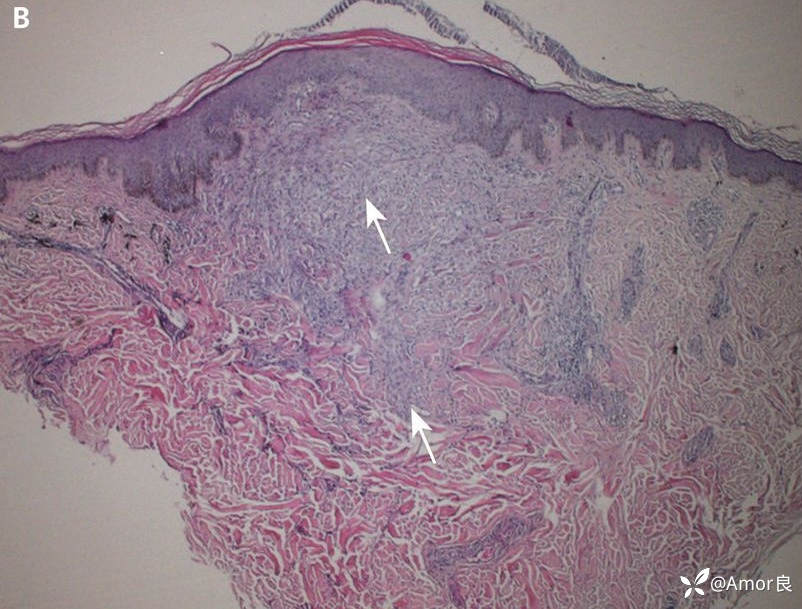

辅助检查:实验室检查:血脂显著升高。甘油三酯 4.52 mmol/L(正常值:0.24-1.70),总胆固醇 10.5 mmol/L(正常值:2.8-5.7)。取文身部位皮损活检。镜下显示:表皮大致正常。真皮层内可见大量结节状聚集的泡沫细胞及散在的多核巨细胞浸润。在毛囊及毛囊周围组织中可见外源性色素(文身颜料)沉积。